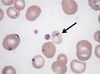

Plasmodium falciparum (ring, trophozoite – note double chromatin dots)

Plasmodium falciparum (ring – note double chromatin dots)

Plasmodium falciparum (ring – note multiple infections)